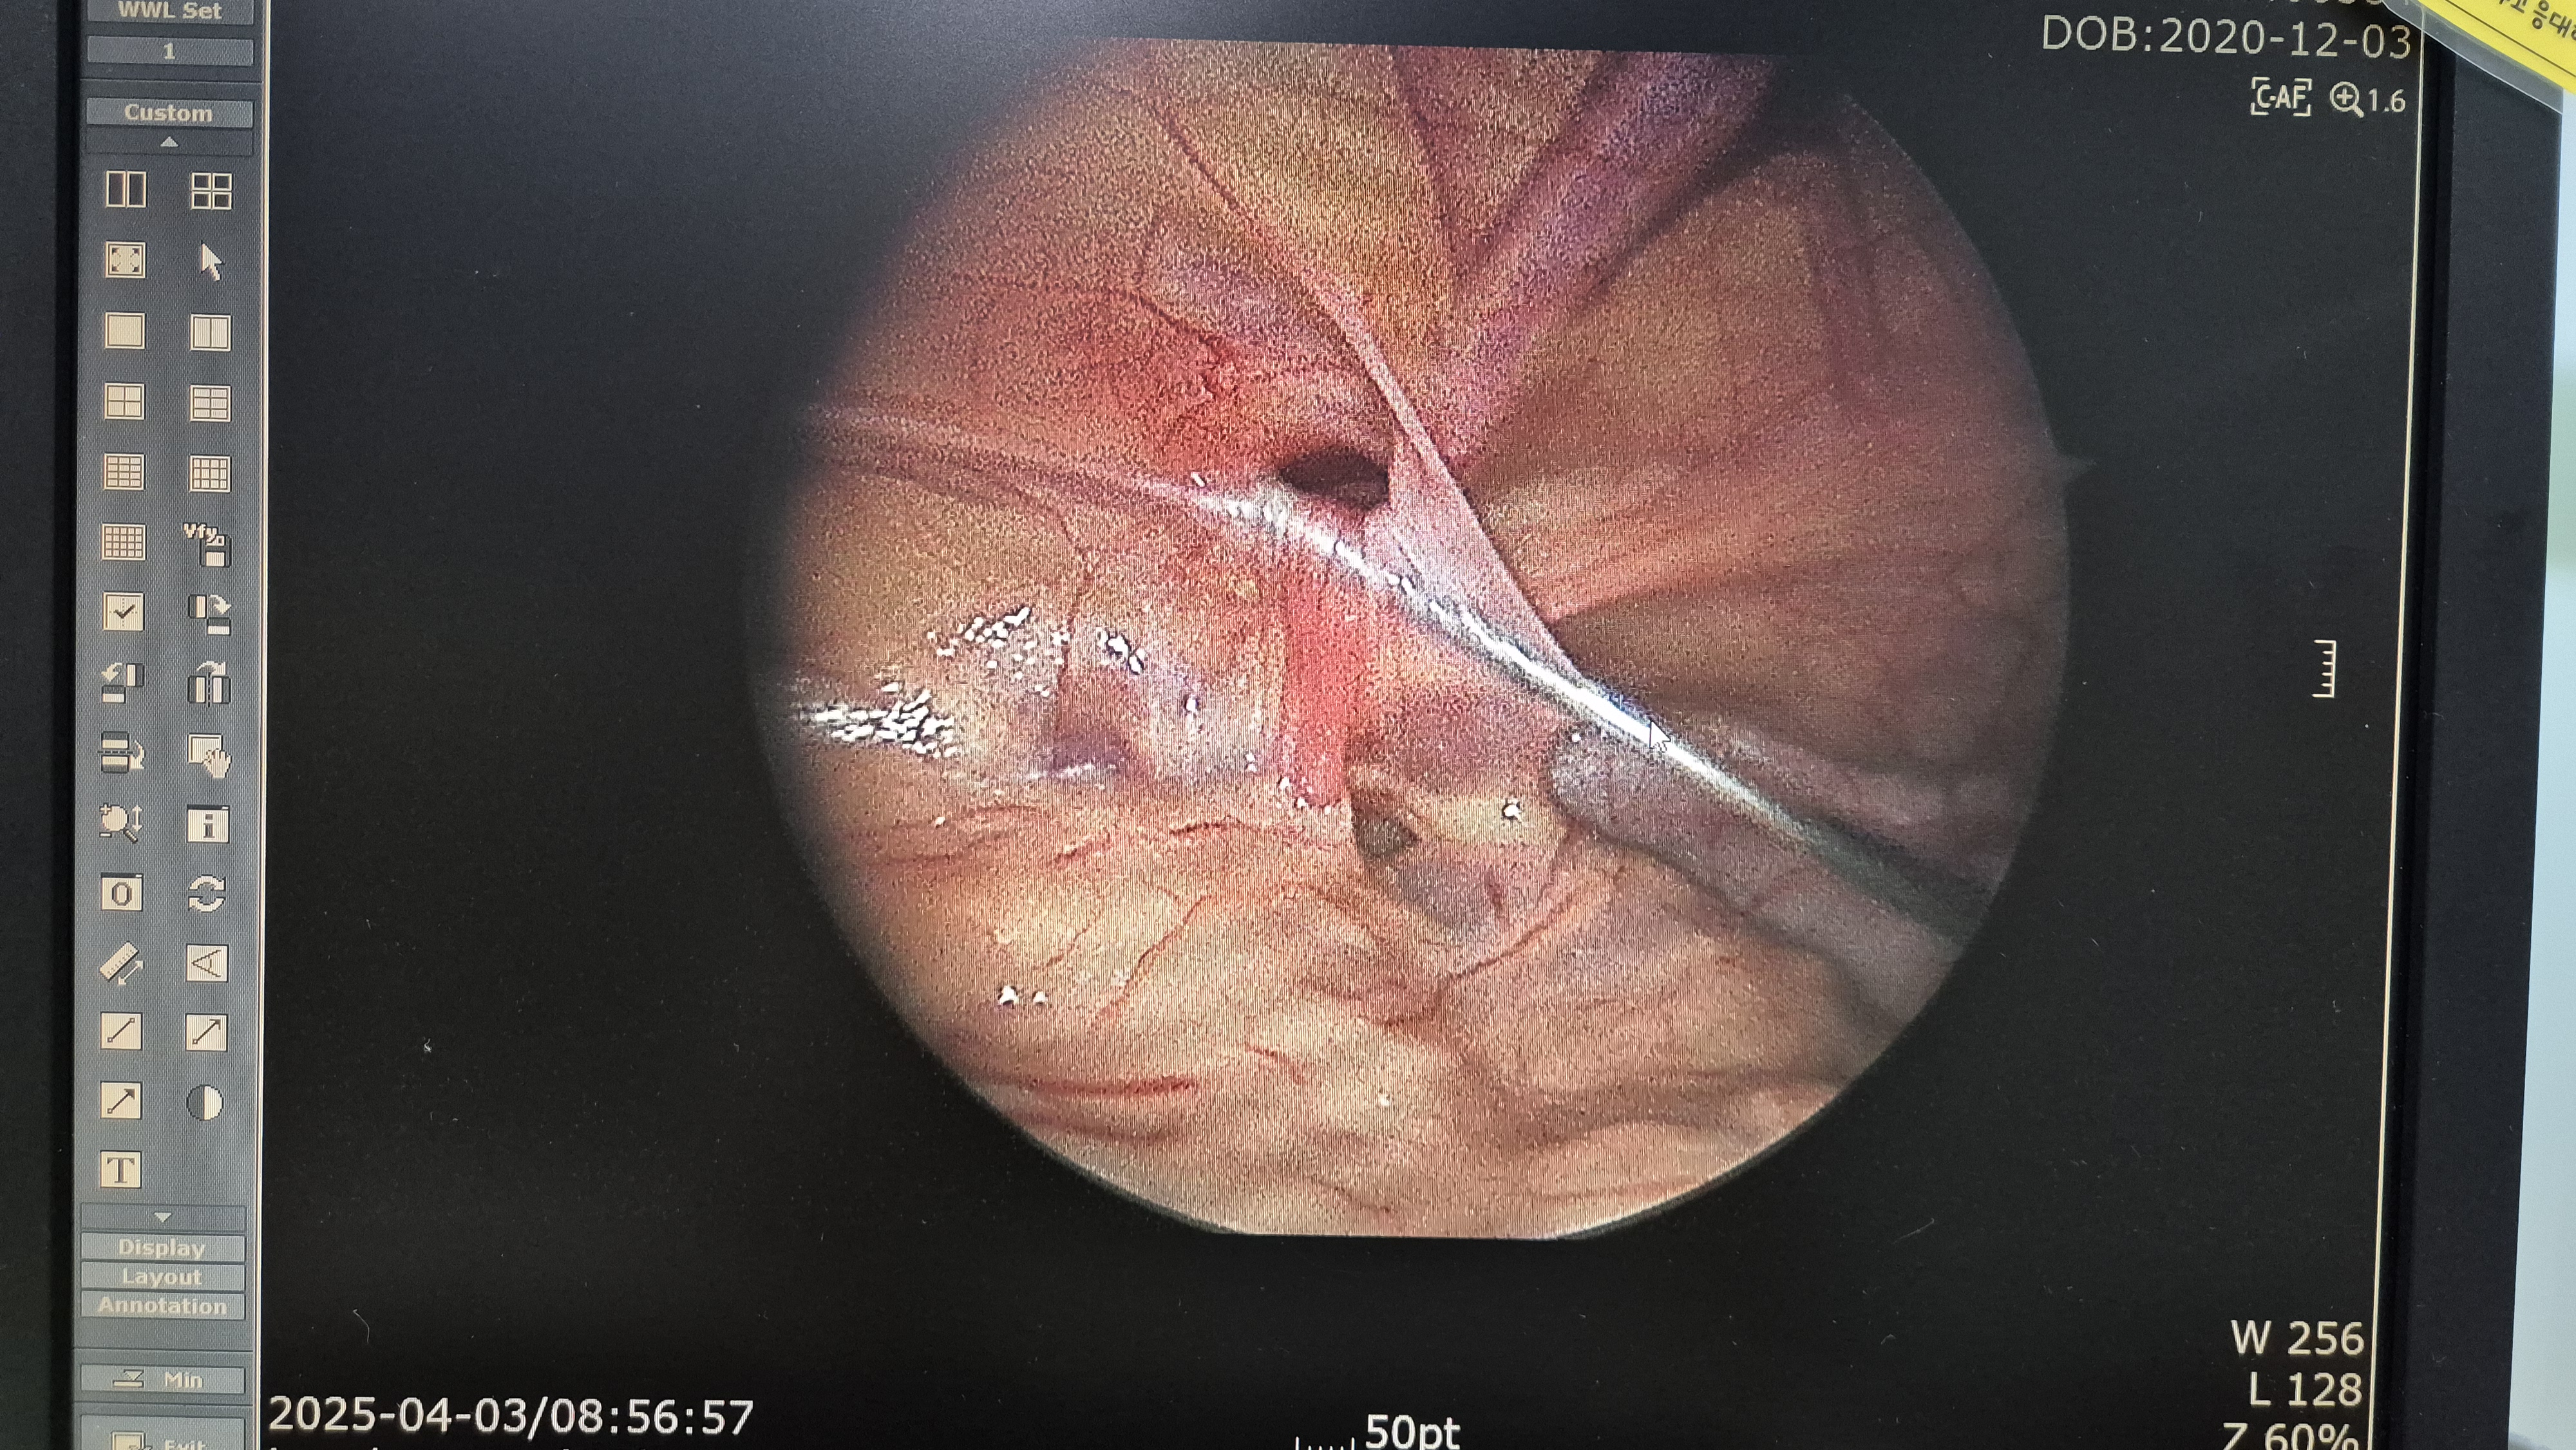

교정중.

교정중.